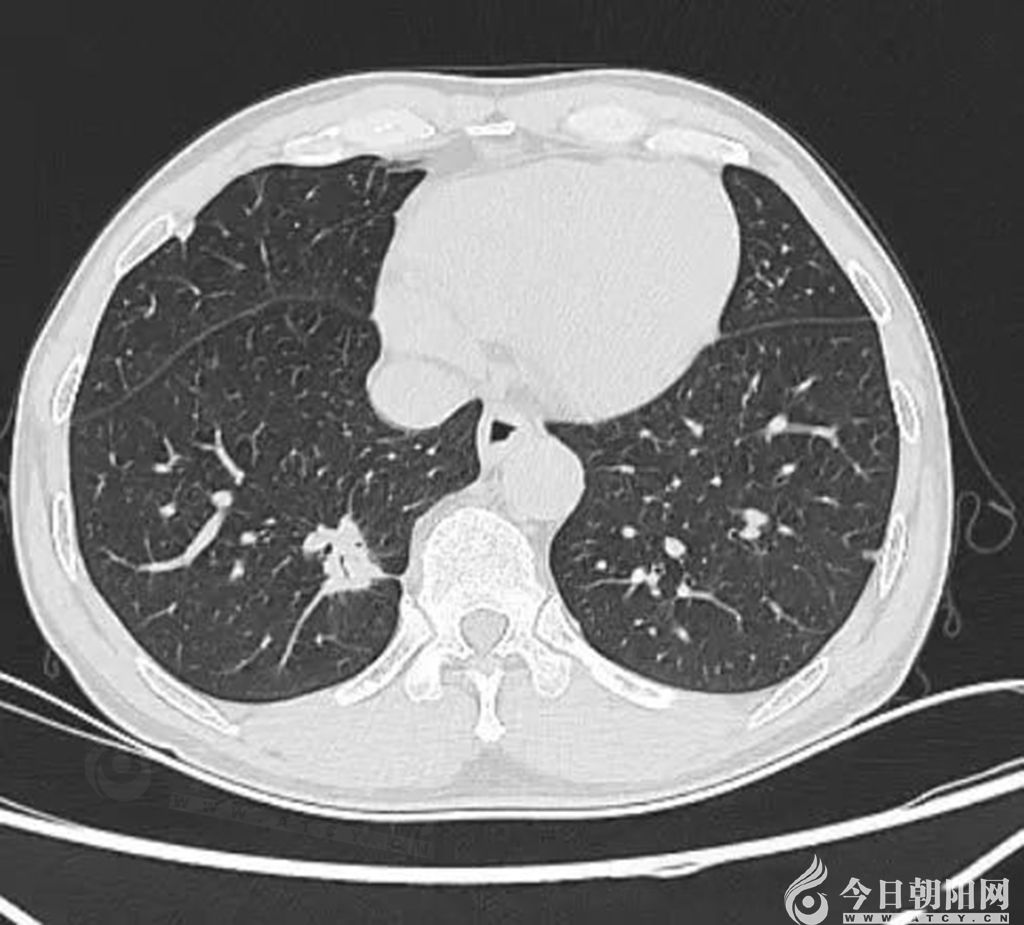

醫(yī)院介入腫瘤科副主任林麗介紹,該名患者為中年男性,因胃部經(jīng)常感到疼痛不適,來到醫(yī)院做胸部增強CT。結(jié)果顯示,患者右肺下葉結(jié)節(jié)灶,考慮肺癌可能。同時,右肺門及縱膈淋巴結(jié)轉(zhuǎn)移可能大,雙肺炎癥、肺氣腫,雙肺多發(fā)微、小結(jié)節(jié),胰管略擴張。此外,頭部MRI顯示,左側(cè)頂葉占位性病變,轉(zhuǎn)移瘤可能大。于是,患者立即到省腫瘤醫(yī)院做進一步檢查。行PET/CT顯示,右肺下葉不規(guī)則結(jié)節(jié)影,代謝增高,惡性病變不除外,患者于中國醫(yī)科大學附屬第一醫(yī)院行超聲引導下導穿刺活檢,病理診斷為惡性腫瘤。

肺部CT